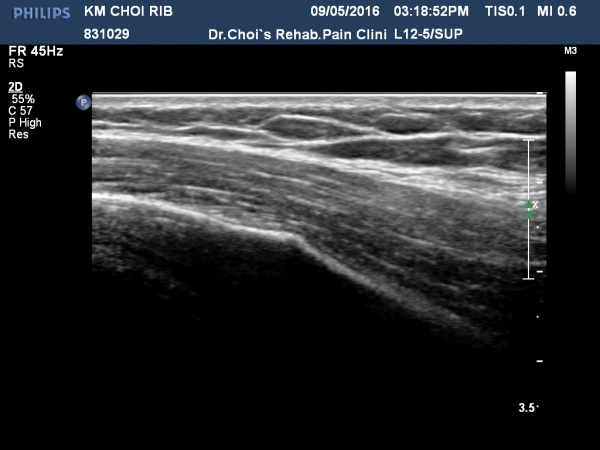

3ÁÖ ÈÄ ÃßÀû°Ë»ç¿¡¼­ °¡°ñ(callus)Çü¼ºÀÌ °üÂûµÈ´Ù(»çÁø 5, 6, 7, 8).

ÃÊÀ½ÆÄ¸¦ ÀÌ¿ëÇÏ¸é ¹æ»ç¼±°Ë»ç³ª ÄÄÇ»ÅÍÃÔ¿µ¿¡¼­µµ º¸ÀÌÁö ¾Ê´Â °¥ºñ»À ¹Ì¼¼ °ñÀýÀÇ Áø´ÜÀÌ °¡´ÉÇÏ´Ù.